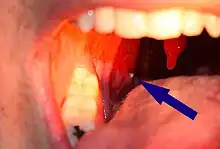

| A tonsillolith lodged in the tonsillar crypt | |